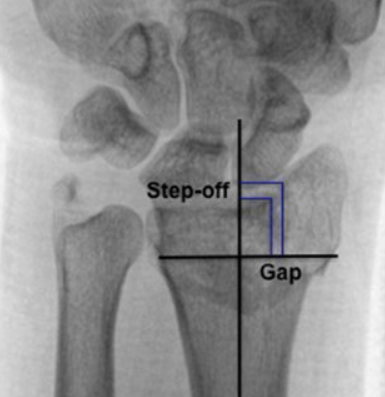

Bước ra và khoảng cách nội khớp: biện pháp trực tiếp của điều isự phù hợp. Bước lệch đề cập đến sự dịch chuyển theo chiều dọc giữa các bề mặt khớp liền kề; khoảng cách đề cập đến sự phân tách theo chiều ngang. Ngưỡng thường được sử dụng để coi mức độ giảm không đủ là bước lệch hoặc khoảng cách khớp > 2 mm.